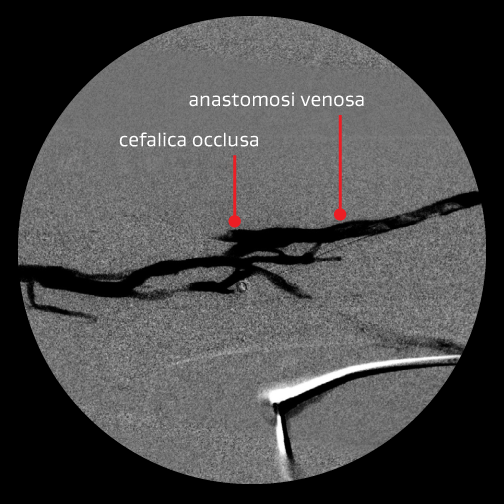

Primo intervento — È stata scelta l'angioplastica percutanea transluminale (PTA) di declotting per trattare la protesi trombizzata

Intervento PTA di declotting:

- La protesi trombizzata era secondaria alla severa stenosi anastomotica venosa.

- Il circuito aveva funzionato bene per quasi due anni.

Motivazione per il trattamento:

- Dare alla lesione un'opportunità di “dichiarare la sua storia naturale”

- KDOQI 6.7 – trattamento della trombosi e della stenosi associata

- 6.7.5 le stenosi devono essere corrette utilizzando l'angioplastica o la revisione chirurgica

Risultato:

- Un buon risultato angiografico iniziale con flusso ripristinato; tuttavia, il paziente si è ripresentato dopo 12 giorni con una protesi trombizzata

Immagini per gentile concessione dei Minneapolis Vascular Physicians. Utilizzate con autorizzazione.